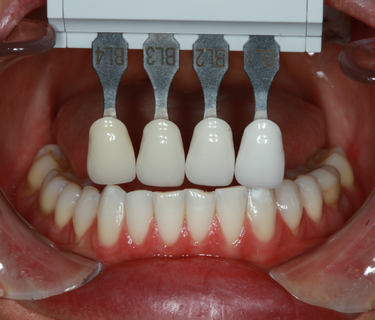

The next step was to bleach Enisa’s remaining teeth that were not involved with the veneer case externally with an in-office teeth whitening treatment (GLO, Glo Science). We were able to brighten her teeth from an initial shade of BL4 to a BL2. After letting the teeth relax for a few days she was stable with a lower teeth shade of BL2/3. (Fig. 20, left top)